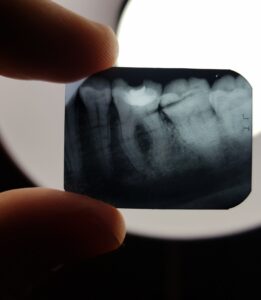

Прицельный снимок зуба – это быстрый, современный метод диагностики полости рта. Рентген помогает врачу правильно ставить диагноз и назначать план лечения.

2. Прицельный снимок. По изображению врач оценивает состояние 1-3 зубов, расположенных рядом. Снимок помогает определять, в каком состоянии находятся корневые каналы, дентин, десна и ткани кости.